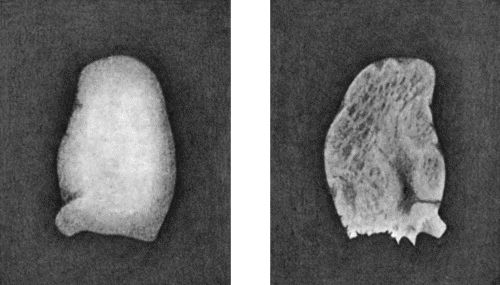

129.Shortening of Middle Finger of Adult, the result of Tuberculous Dactylitis in Childhood 461

130.Syphilitic Disease of Skull 463